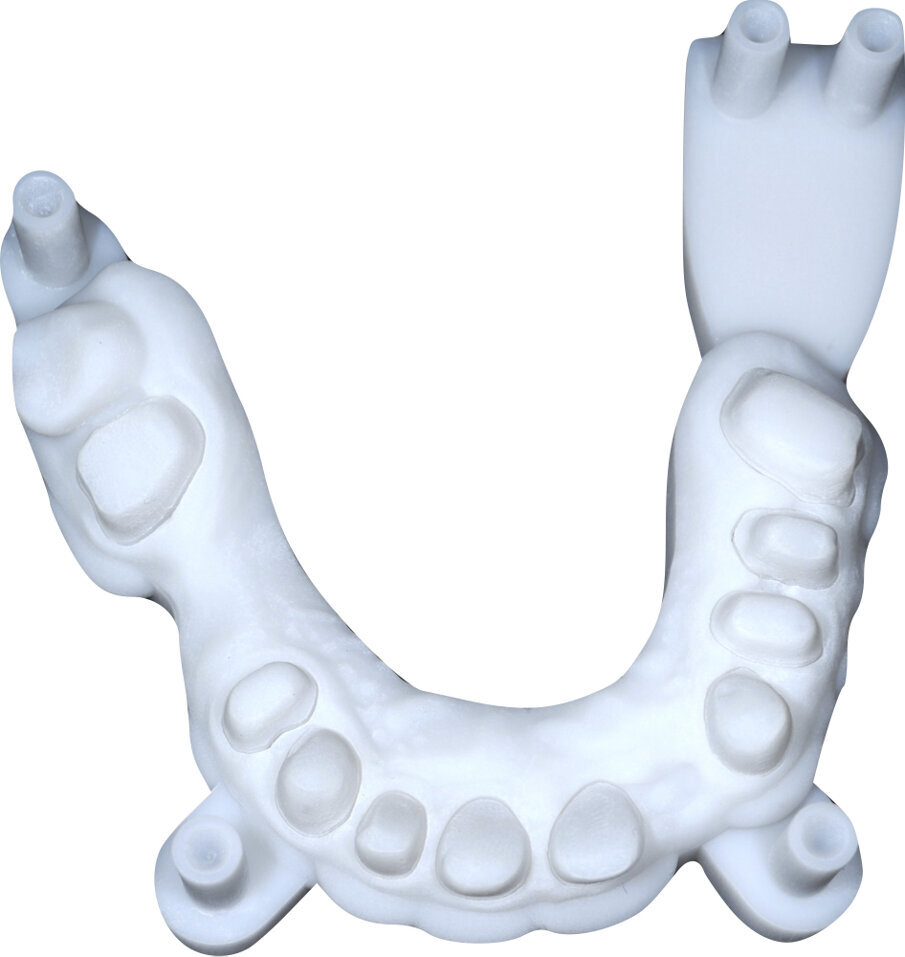

Si esegue perciò cefalometria (Fig. 8) su radiografia latero-laterale (Fig. 9) e axiografia dei movimenti limite (Cadiax Compact, Gamma Dental) (Fig. 10) per la programmazione di un articolatore a valori medi (Artex TR, AmmanGirrbach) e montaggio dei modelli con arco faciale, che confortano nella produzione di un primo provvisorio prelimatura con rialzo arbitrario della VDO di 5 mm sull’asta incisale e miglioramento di OB e OJ, a scopo pre-terapeutico interlocutorio e di immediata risoluzione estetica. Conclusa la necessaria terapia causale e restaurativa viene eseguita la scansione intraorale delle arcate (TRIOS 3 Pod, 3Shape) (Figg. 11-14) e del rapporto articolare con cera di RP (Fig. 15). La scansione è stampata (VisiJet RWT, 3D Systems) con monconi sfilabili tramite stampante 3D (ProJet MJP 2500 Plus, Selltek) (Figg. 16-20), i modelli derivanti sono zoccolati e montati con cere di RP e arco faciale su articolatore a valori individuali (Reference SL, Gamma Dental). La programmazione dell’articolatore derivante dalla registrazione axiografica è ora eseguita come da indicazioni del software (Gamma Dental software, sia per l’uso degli inserti condilari ed incisali, sia per la definizione degli angoli di SCI e di Bennet (Fig. 21). Lo spazio protesico risultante a una VDO adeguata alla riabilitazione dei denti anteriori vitali, con anatomia non ulteriormente modificabile, è insufficiente per uno stabile ripristino dei rapporti occlusali, specie nei tragitti funzionali. Si decide perciò di impiegare due inserti rossi di programmazione di protrusiva (+2 mm) per riposizionare la mandibola in TRP (Figg. 22, 23).